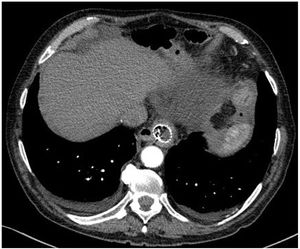

However, 24 h later, he was readmitted for haematemesis with normal CT angiography (Fig. 1), and endoscopy was performed to control the haemorrhage by means of clips without adequately visualising the endoprosthesis. After a new endoscopy at 8 h, the endoprosthesis was removed and haemostasis was checked, apparently adequate. Five days later, the patient presented with a new haemorrhage with instability, and endoscopic control was not achieved, so urgent open surgery was decided on suspicion of aorto-oesophageal fistula. The review of the CT angiography, prior to removal of the endoprosthesis, supports the diagnosis by showing the proximity of the proximal portion of the endoprosthesis to the aorta, as shown in the 3D reconstruction (Fig. 2). During surgery, the fistula was confirmed and repaired with direct aortic suture. For visualisation, the oesophago-jejunal anastomosis had to be undone and oesophagectomy, cervical oesophagostomy and feeding jejunostomy were performed.